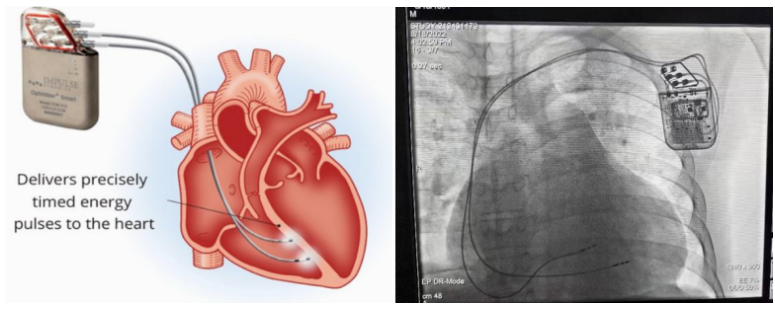

①植入式心臟復(fù)律除顫器

Implantable Cardioverter Defibrillator,ICD

植入式心臟復(fù)律除顫器是一種具有除顫功能的高級(jí)起搏器,是一種體積小、能植入患者胸部皮下組織的醫(yī)療設(shè)備。慢性心衰患者易發(fā)生室性心動(dòng)過速或心室顫動(dòng),導(dǎo)致心源性猝死(SCD)。ICD 則能在幾秒內(nèi)自動(dòng)識(shí)別并治療快速室性心律失常,通過低能量心臟轉(zhuǎn)復(fù)和高能量除顫等功能,顯著降低惡性室性心律失常引起的猝死風(fēng)險(xiǎn)??杉皶r(shí)自動(dòng)為患者轉(zhuǎn)復(fù)心律,通俗地說就是裝在體內(nèi)的自動(dòng)除顫儀。

心臟再同步化治療,指雙心室起搏器,是通過雙心室同步起搏的方式,幫助心衰患者實(shí)現(xiàn)正常起搏的裝置。CRT包括一個(gè)口袋大小的脈沖發(fā)生器和三根電極導(dǎo)線,可被植入人體。通過監(jiān)測(cè)心律,在發(fā)現(xiàn)異常后,信號(hào)發(fā)生器發(fā)送電流脈沖,刺激心室重新同步,從而改善癥狀,提高患者的心臟泵血效率。目前有兩種類型的CRT裝置:植入式心臟再同步治療起搏器(CRT-P)和植入式心臟再同步治療除顫器(CRT-D)。主要區(qū)別在于后者除了改善心臟收縮同步性外,還具備除顫功能,能及時(shí)處理危及生命的室性心律失常,避免猝死。